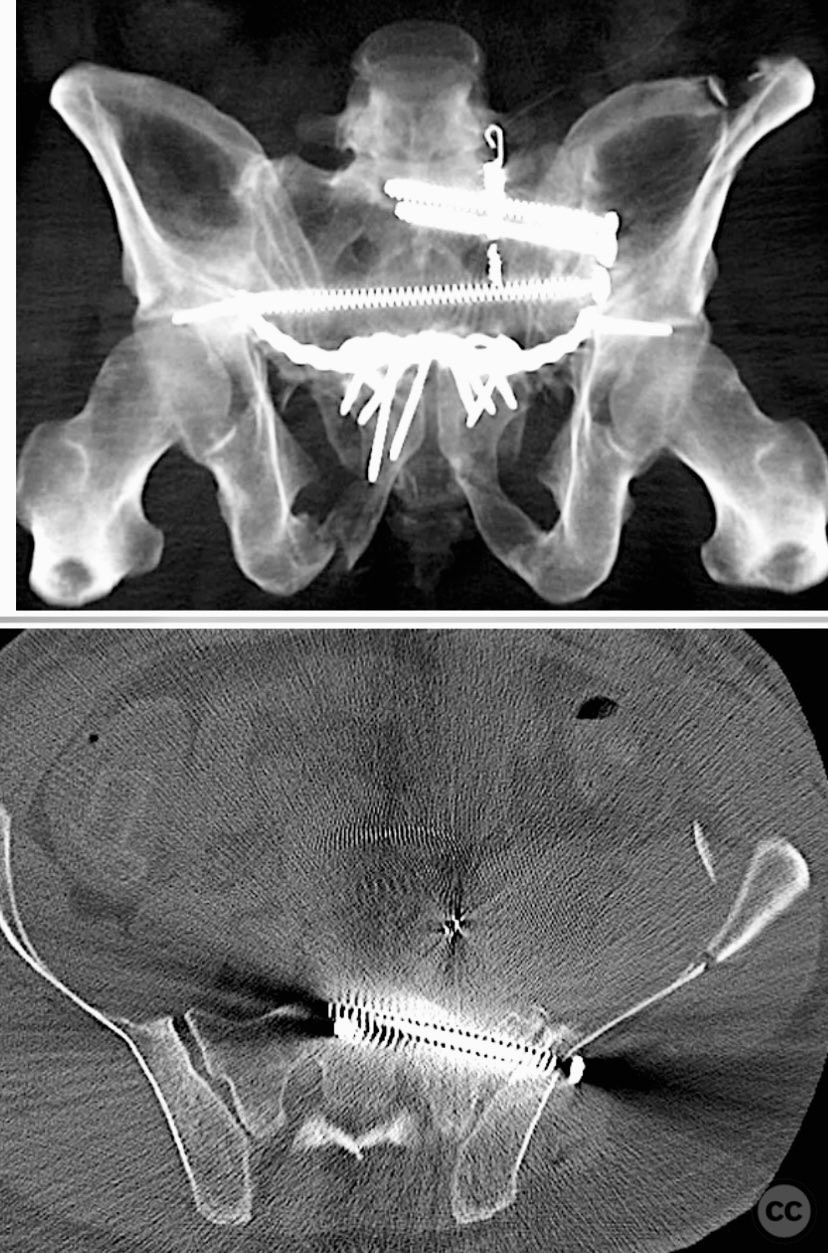

Clinical and radiological findings:  A 42-year-old male sustained a high-energy motor vehicle accident resulting in an unstable pelvic ring injury (AO/OTA 61-C1.3) with hemodynamic instability and associated intraperitoneal bladder rupture. Initial computed tomography demonstrated a complex anterior pelvic ring disruption and a posterior sacral fracture with contrast extravasation and blood within the fracture site. The patient was hemodynamically unstable on presentation.

Planning remarks:  The preoperative plan included multidisciplinary management with urology for bladder repair, followed by open reduction and internal fixation of the anterior pelvic ring via an anterior approach. Subsequent posterior pelvic stabilization was planned after initial resuscitation and anterior fixation, utilizing a posterior approach for direct sacral reduction and percutaneous iliosacral screw fixation.

Anatomical surgical approach:  The anterior approach utilized a Pfannenstiel incision to access the symphysis pubis and pubic rami, with subperiosteal dissection of the rectus abdominis and exposure of the retropubic space for reduction and fixation. For posterior sacral ORIF, a midline longitudinal incision was made over the sacrum, with subperiosteal elevation of the paraspinal musculature to expose the sacral fracture. A tenaculum clamp was applied for direct reduction, followed by percutaneous insertion of iliosacral screws under fluoroscopic guidance.

The case was notable for initial successful multidisciplinary management of both hemodynamic instability and intraperitoneal bladder injury, allowing for staged surgical intervention. Despite accurate anterior pelvic reduction and fixation, postoperative imaging revealed worsening posterior sacral displacement, necessitating subsequent posterior open reduction. The use of a tenaculum clamp facilitated direct anatomical reduction of the sacral fracture prior to iliosacral screw fixation. The presence of an embolic coil from prior angioembolization did not impede surgical access or hardware placement. This case demonstrates that initial anterior pelvic ORIF does not complicate or preclude subsequent routine posterior pelvic ORIF in complex unstable ring injuries.

Orthopaedic implants used:   Anterior pelvic reconstruction plate, iliosacral cannulated screws, tenaculum reduction clamp